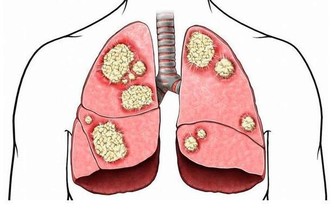

這類體質的人,體溫會比一般人來得低,測量到的體溫大多會低於正常體溫36.5~37 度。長期體溫偏低的結果,就會導致人體免疫力下降3成,比一般人更容易得到感冒、過敏,又或是其他不適的情形。

常出現的其他不適,包括了四肢冰冷、腸胃功能較弱、容易倦怠、活動力不佳等情形,甚至會引發憂鬱症。